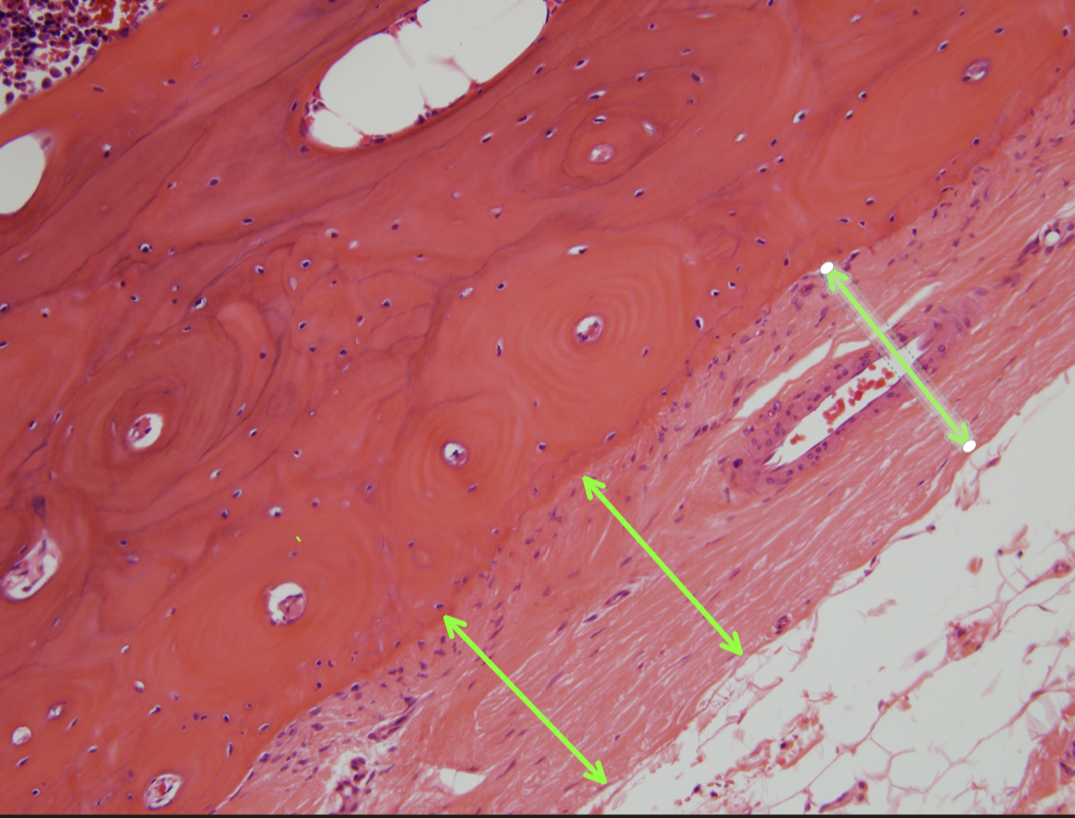

Q

Identify this structure:

23

Identify these structures:

24

Identify this region:

25

Haversian Canals

26

osteocytes

27

osteoblasts

28

cartilage

29

osteoclast